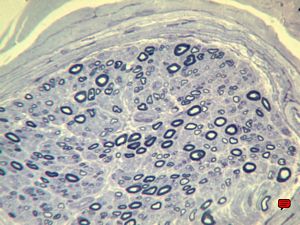

F,12y. | hypertrophic (onion bulb) neuropathy - n.suralis

F,12y. | hypertrophic (onion bulb) neuropathy - n.suralis

F,12y. | hypertrophic (onion bulb) neuropathy - n.suralis